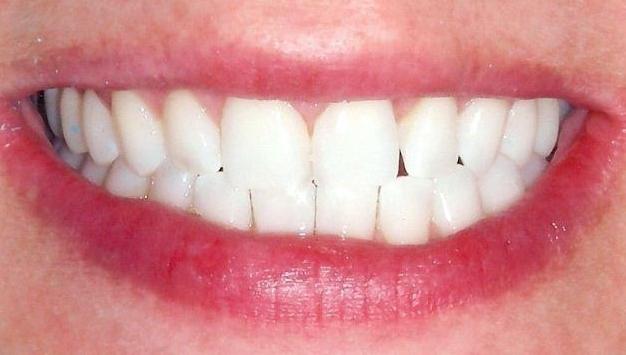

Smile Makeover with Composite Resin Veneers and Reshaping

Reshaping and composite veneer is often the most cosmetic and conservative approach to smile rehabilitation. This makeover was completed in a single visit, and no healthy tooth structure was removed.